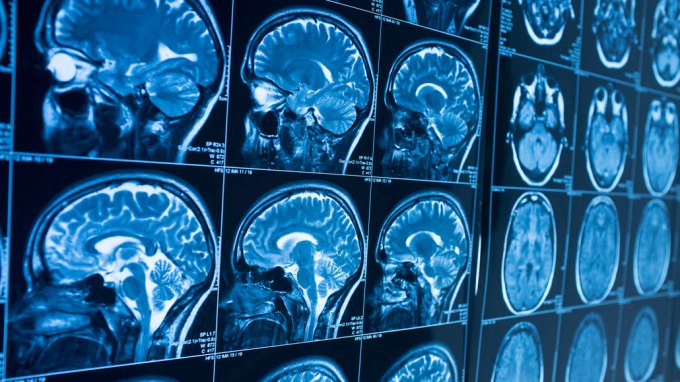

Electrodes show a glimpse of memories emerging in a brain

Nerve cells in an important memory center in the brain sync their firing and create fast ripples of activity seconds before a recollection resurfaces.

Alzheimer’s targets brain cells that help people stay awake

Nerve cells in the brain that are tied to wakefulness are destroyed in people with Alzheimer’s, a finding that may refocus dementia research.